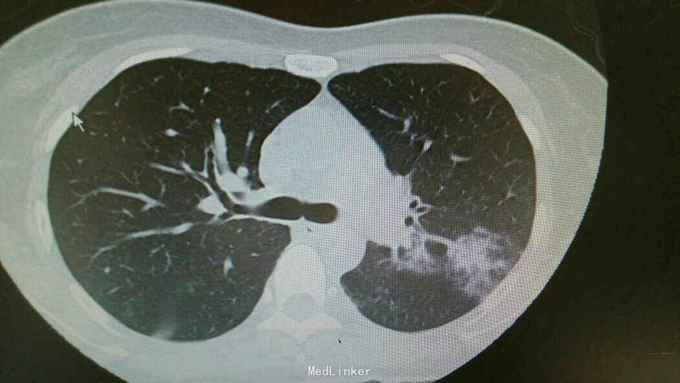

主诉:发热伴咳嗽咳痰6天。 病史:患者6天前无明显诱因出现发热,最高体温39.3度,伴有咳嗽,咳痰,咳黄色粘液痰,无畏寒寒战,无头晕头痛,为求治疗,入住我科。

查体:双肺呼吸音粗,双下肺可闻及湿罗音。心腹无异常。 辅查:双肺炎症,左侧可见多发斑片状,渗出实变影,边缘模糊,部分邻近胸膜,粘连。

诊断:肺炎支原体费炎。 治疗:入院予以抗感染,止咳化痰等治疗。治疗后复查胸片,左中下肺炎症好转。